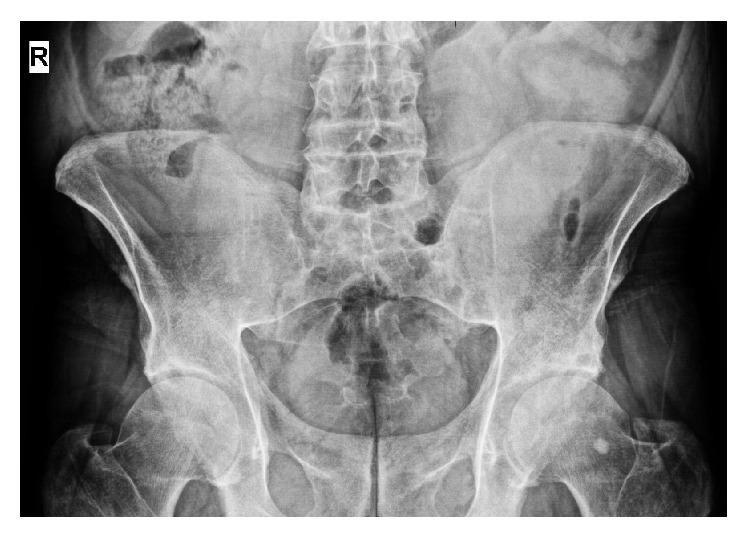

Ankylosing spondylitis (AS) is a systemic disease primarily characterized by the inflammation of sacroiliac joints and axial skeleton. Neurofibromatosis type 1 (NF1) is a multisystem genetic disease which is characterized by cutaneous findings, most importantly café-au-lait spots and axillary freckling, by skeletal dysplasia, and by the growth of both benign and malignant nervous system neoplasms, most notably benign neurofibromas. In this case report, we present a 43-year-old male with AS and NF1.

强直性脊柱炎(AS)是一种全身性疾病,主要特征为骶髂关节和中轴骨骼的炎症。1型神经纤维瘤病(NF1)是一种多系统遗传病,其特征包括皮肤表现,最重要的是牛奶咖啡斑和腋窝雀斑,骨骼发育异常,以及良性和恶性神经系统肿瘤的生长,最显著的是良性神经纤维瘤。在本病例报告中,我们介绍了一名患有AS和NF1的43岁男性。